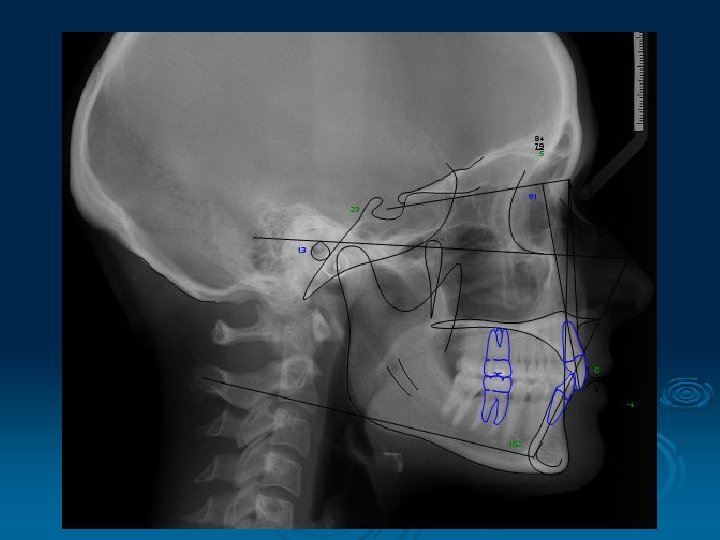

Telerentgen

Cephalometric point, plane, line and angles used in dentistry S (Sella) midpoint of sella turcica N (Nasion) most anterior point on fronto-nasal suture Or (Orbitale) most inferior anterior point on margin of orbit Po (Porion) upper most point on bony external auditory meatus ANS (Anterior Nasal Spine) PNS (Posterior Nasal Spine)

Go (Gonion) most posterior inferior point on angle of mandible Me (Menton) lower most point on the mandibular symphysis A (A point) position of deepest concavity on anterior profile of maxilla B (B point) position of deepest concavity on anterior profile of mandibular symphysis

Frankfort Plane: Po - Or Equivalent to the true horizontal when patient is standing upright Maxillary Plane: PNS - ANS Gives inclination of maxilla relative to other lines/planes Mandibular Plane: Go - Me Gives inclination of mandible relative to other lines/planes

Important lines: S - N line N - A line N - B line Important angles: SNA SNB ANB Indicates position of maxilla / mandible to each other and to the cranial base